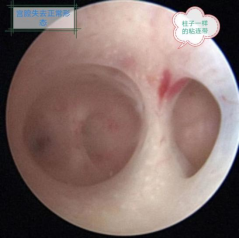

从结构上看,子宫底两侧角各见一个精致玲珑的“窗户”--输卵管开口,它向外通向走廊一般的输卵管管腔,而这里则是精子与卵子相遇的“必经之路”,窗口敞开、道路通畅,是受精卵顺利形成并到达宫腔的前提和保障。

然而,却有一种疾病,让这精致的殿堂变成了“毛坯房”,“砖墙”裸露,遍布“蛛网”,房间里横七竖八的“柱子”,狭窄的空间让经血淤堵,让精子在里面迷失方向,让孕囊找不到着床的地方。好不容易形成的小胚胎因为“土壤”贫瘠而发育不良。

宫腔镜检查是诊断宫腔粘连的金标准,宫腔镜可以直接观察子宫内部情况,从而了解到粘连的具体情况,便于医生最终的确诊。